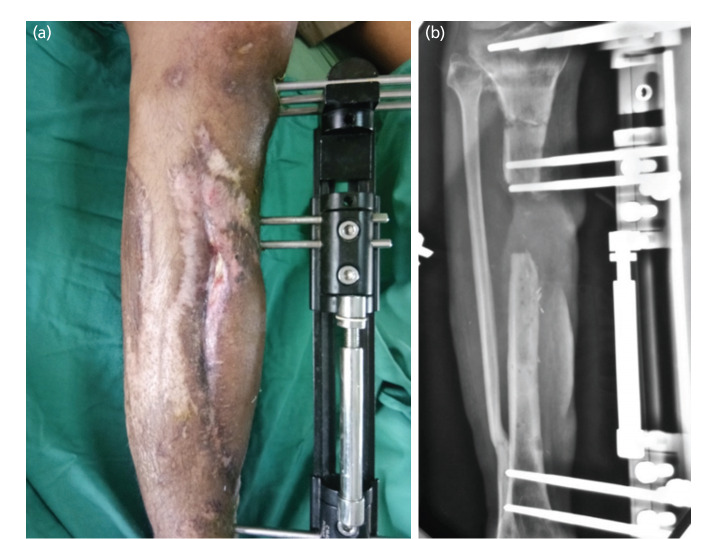

Introduction: Bone loss is a serious complication following an open fracture or fracture-related infection in the tibia. Treatment with Ilizarov bone transport in this condition is preferred because it minimises additional soft tissue injury and is able to close the bone and soft tissue defects through distraction osteogenesis. The objective of this study is to evaluate the relationship between functional outcomes of patients with tibial bone loss treated with Ilizarov bone transport and return to work.

Materials and methods: A cross-sectional study among 40 patients was carried out in 2 public hospitals. Patient records and radiographs were reviewed for information on the initial injuries, treatment, union of bone, and complications while on treatment. The clinical outcomes were evaluated with ASAMI Bone grading system while the functional outcome of the affected limb was assessed using Lower Extremity Score (LEFS) and ASAMI Functional grading system at least 10 months after the removal of the Ilizarov external fixator.